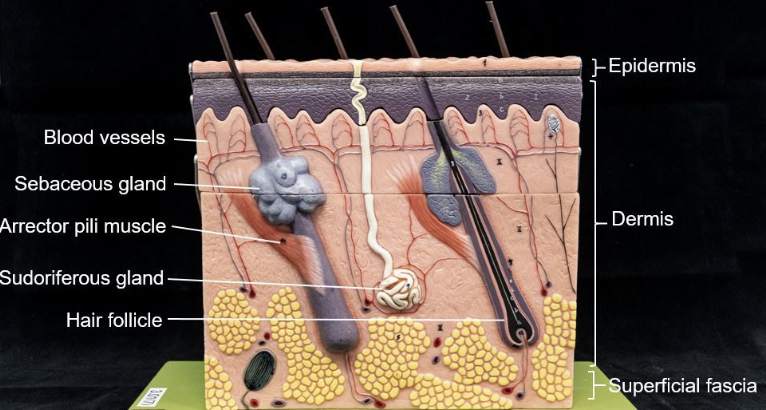

New cards

Label

Label

Thin skin